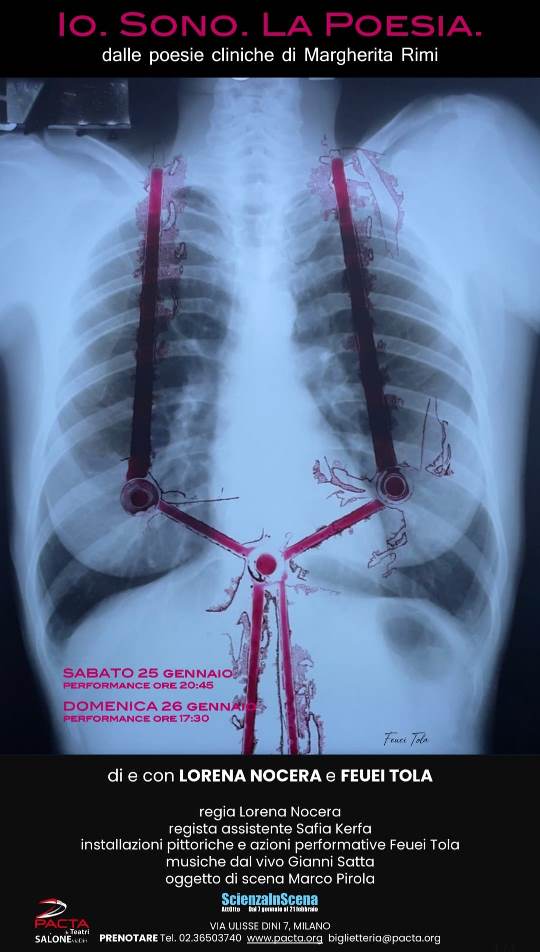

Quale è la verità del nostro corpo, l’ultima possibile? Che distanza c’è fra di essa e la verità della nostra mente? Coincidono davvero senza inciampare mai? La poesia può essere il mezzo per colmare questa distanza: può inventare per tutti noi un’eternità oltre la finitezza cui siamo destinati, oltre la nostra imperfezione, e divenire la più alta forma di cura della nostra persona e della nostra vita. Un medico/scrittore alle prese con i suoi pazienti e un’artista si misurano con queste preziose domande in un fitto dialogo fra arte e parola, realtà e racconto, immagine e musica.

In passato mi chiedevo come mai il linguaggio scientifico emergesse solo in parte nei miei testi. Poi maturando la mia esperienza umana e professionale, si evolveva anche la mia esperienza poetico linguistica. Lo scambio tra sapere medico – scientifico e la poesia si è fatto più intenso, si è fatto dialogo e ricerca di verità, conoscenza, sentimento, senso di stare al mondo.